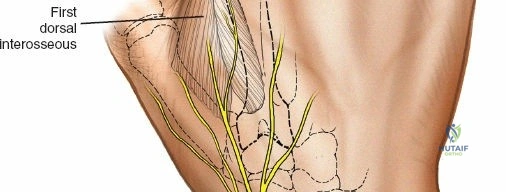

Wrist and Metacarpal Safe Zones

For spanning wrist fixators, distal pins are placed in the second metacarpal. The safe zone is the dorsoradial aspect of the second metacarpal base and shaft. The first dorsal interosseous muscle and extensor tendons must be respected. The radial artery courses proximally in the anatomic snuffbox and must be avoided during basal metacarpal pin insertion.

Metacarpal Pin Placement

1. Make two 1 cm incisions over the dorsoradial aspect of the second metacarpal.

2. Dissect bluntly, protecting the dorsal sensory branches of the radial nerve and the extensor tendons.

3. Place the tissue sleeve at a 45-degree angle to the dorsal and lateral planes to maximize purchase in the metacarpal shaft.

4. Pre-drill and insert two 3.0 mm pins.